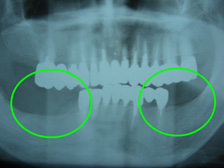

従来のレントゲンのみで診断する平面画像では、内部の骨の状態を正確に把握することが困難でした。

シュミレーションでは、歯科用CTで撮影した画像を処理し、レントゲン画像では分からなかった骨の形や量などを把握でき、正確な診断が可能となります。

また、3D画像は患者様が見ても比較的わかりやすいので、治療の説明もより理解していただけ、充分に納得した上で、手術を受けていただくことができます。

| 治療前 | 治療後 |

|  |  |

| 治療前 | 治療後 |

|  |  |

| 治療前 | 治療後 |

治療前

治療中

治療後